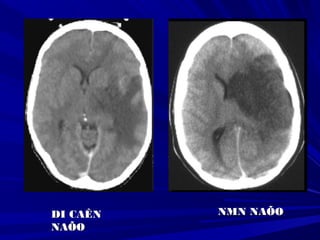

DI CAÊNDI CAÊN

NAÕONAÕO

NMN NAÕONMN NAÕO